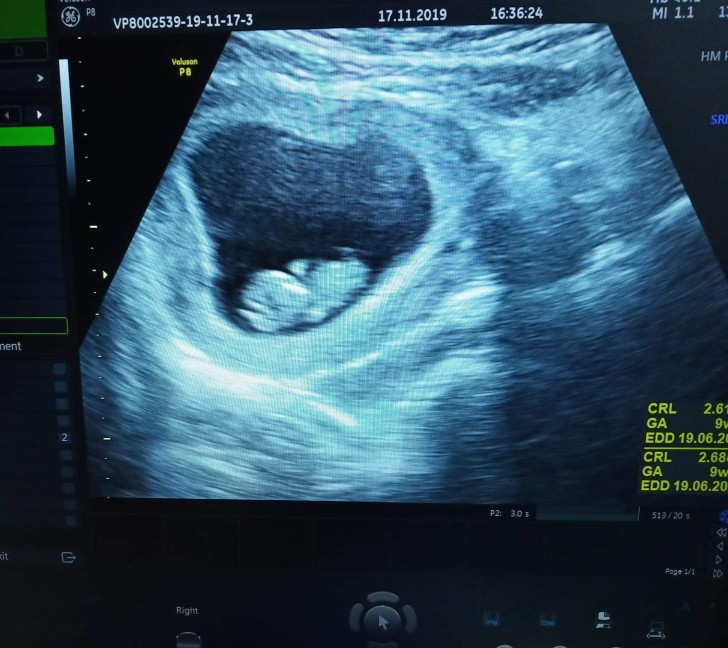

มีแม่ๆท่านไหนเคยซาวตอน9วีคแต่ไม่เจอน้องบางคะ เจอแต่ถุงตั้งครรภ์ หมอนัดอีก1อาทิตซาวใหม่ กังวลมากเลยคะ กลัวลูกไม่อยู่กับเรา

ตอน 9w บ้านนี้จ้า สู้ๆนะคะแม่